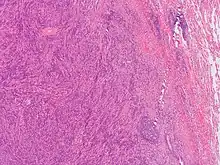

This image was originally posted to Flickr by Pulmonary Pathology at https://flickr.com/photos/30950973@N03/5601450952 (archive). It was reviewed on 3 October 2019 by FlickreviewR 2 and was confirmed to be licensed under the terms of the cc-by-sa-2.0.

General image of plasma cell granuloma that was classified in a broader category of inflammatory pseudotumor. Original author of image was: Yale Rosen from USA[10]